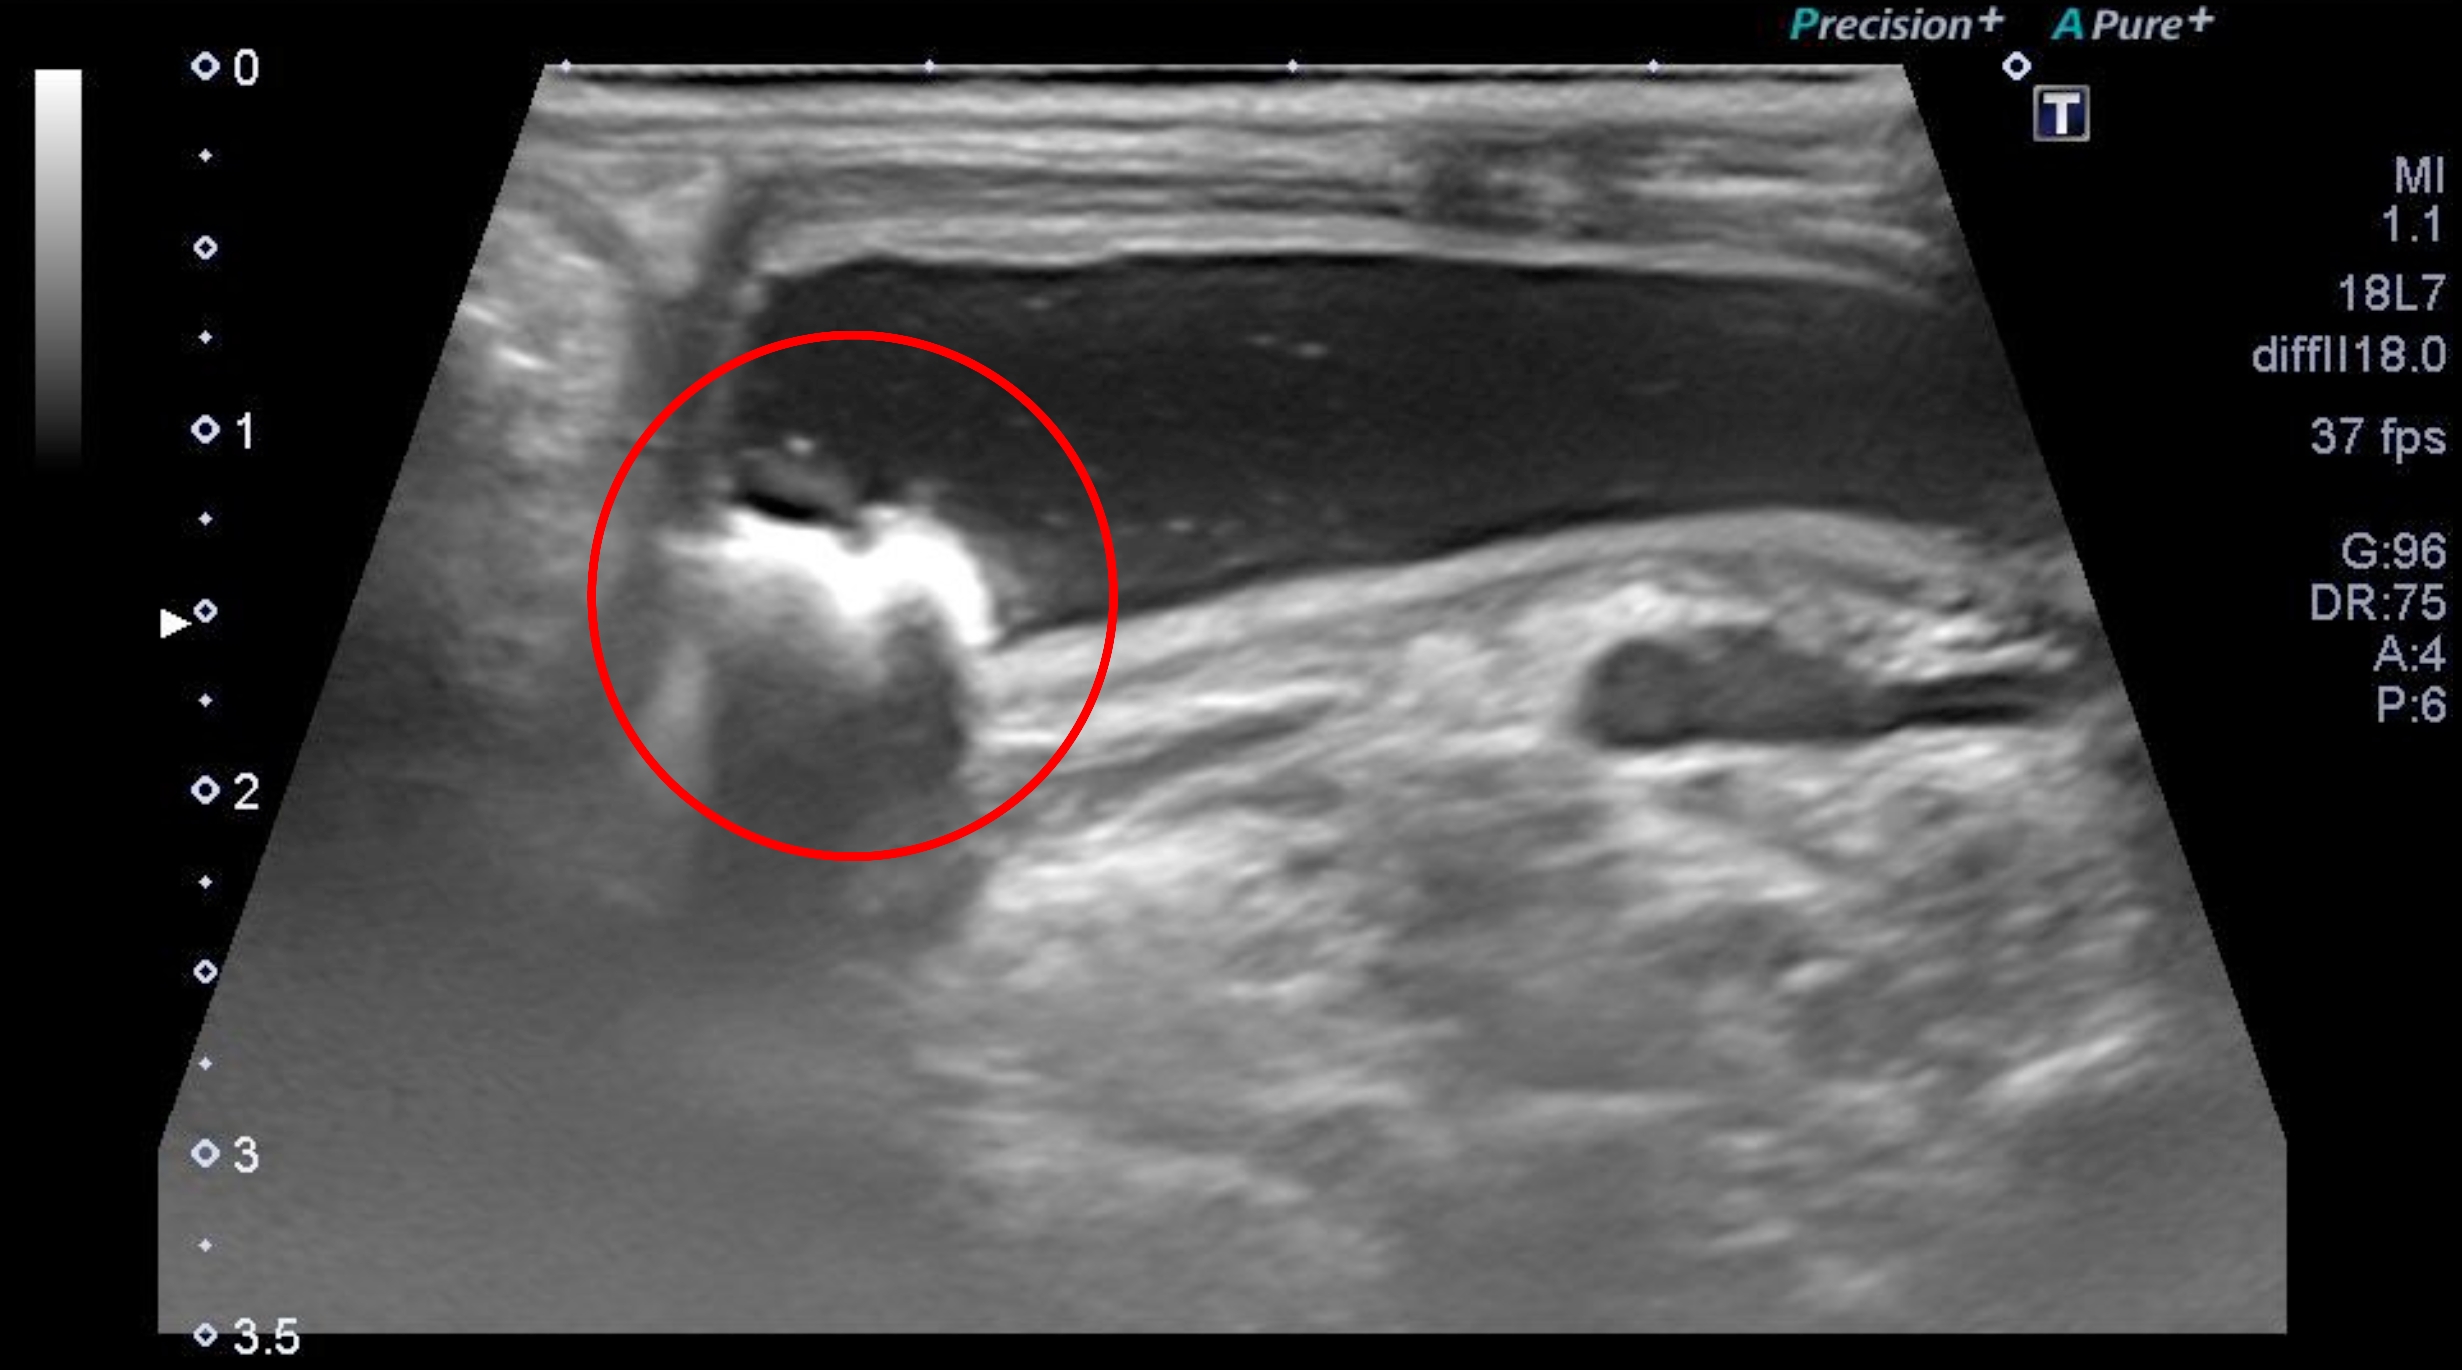

③超音波検査

結石の有無(特に尿管結石)、水腎症(閉塞が起こることで腎臓に尿が溜まり拡張してしまう病気)の有無を確認します。

【12歳去勢済の犬 膀胱のエコー画像】